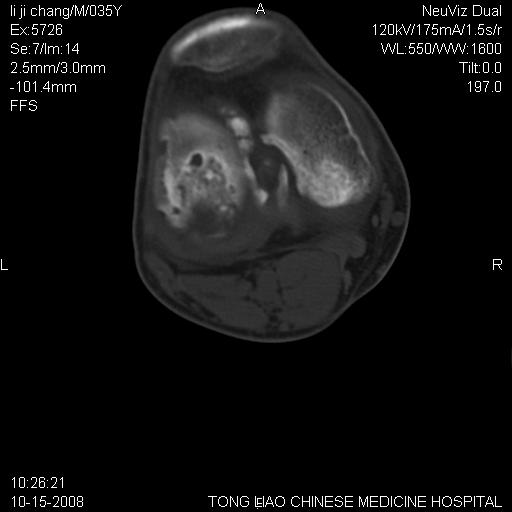

男,35岁,骨科诊断骨性关节炎。继往使用过激素,现股骨头坏死。膝关节病变,请会诊

一元论-----亦考虑为坏死

支持考虑无菌坏死

支持无菌坏死伴退行性骨关节病.

剥脱性骨软骨炎:是一种关节下软骨及软骨下骨缺血性坏死。

支持 无菌性坏死伴退行性骨关节病。

支持无菌坏死伴退行性骨关节病